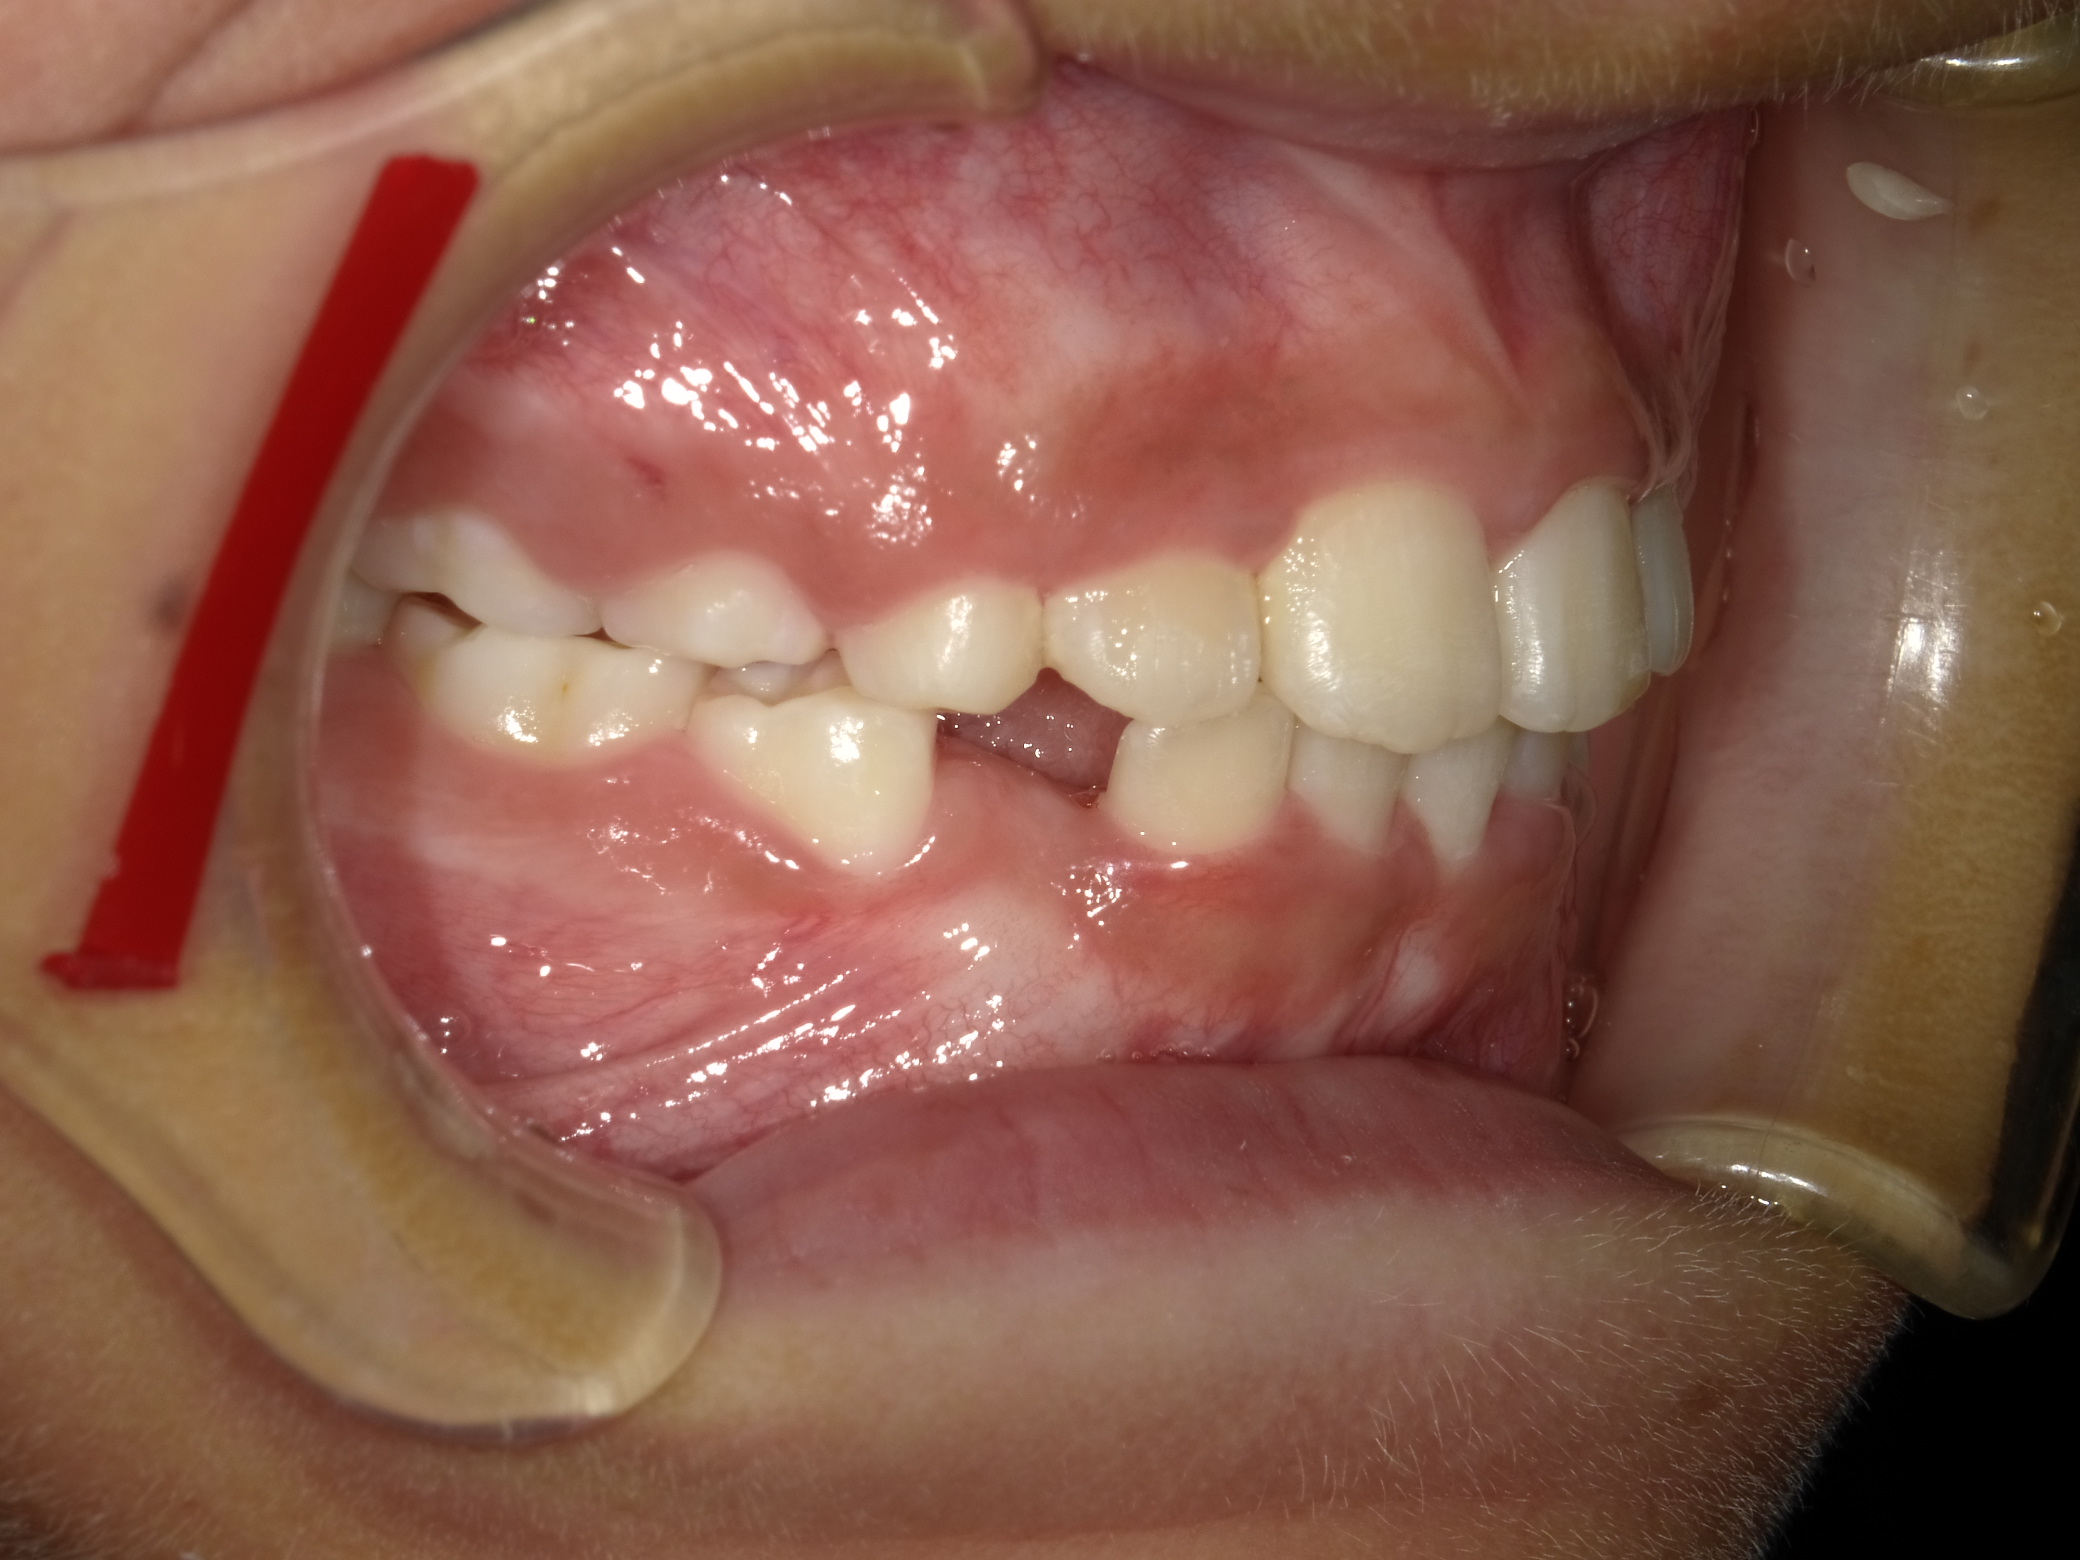

9歳男性 スペース不足(永久歯が並ぶ場所がない)・交叉咬合(一部分だけかみ合わせが反対)